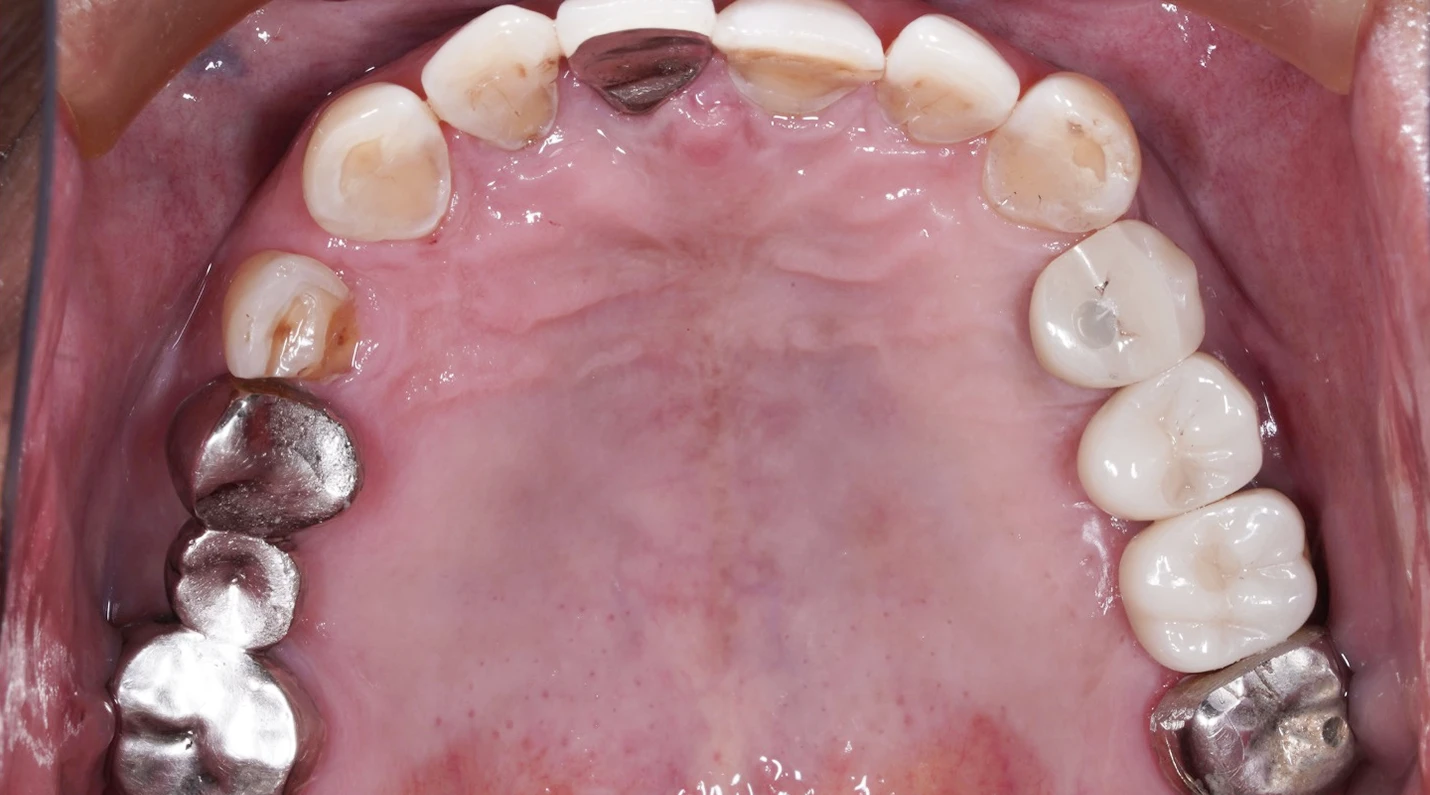

AFTER

インプラント治療を長期的に成功させるためには骨の状態は大変重要です。

抜歯後に歯槽堤温存術を行うことは非常に重要です。患者様は複数回の手術に耐えて大変頑張っていただけました。

これからはメインテナンスのフェーズに入ります。定期的なクリーニングと咬合チェックを怠らないことで、インプラント周囲炎の発症リスクを大幅に抑えられます。

長きに渡りインプラントを使用できるようしっかりと経過を追わせて頂きます。